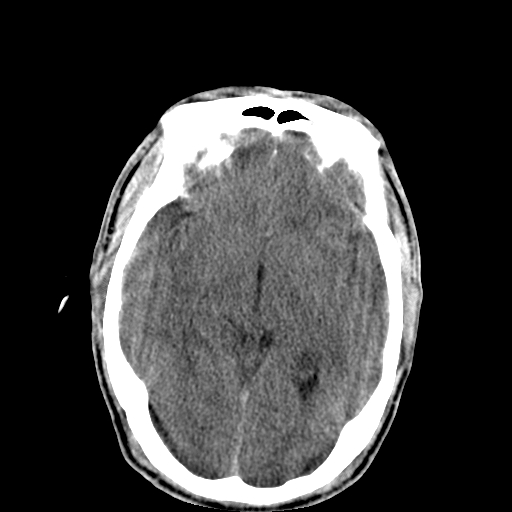

以下是引用李衡钧在2008-9-18 17:37:00的发言:[br]脑质内见两个低密度灶,其内见点状高密度。[br]考虑脑囊虫。建议增强或进一步检查确诊。

以下是引用chmh在2008-9-18 18:45:00的发言:[br]考虑脑囊虫病可能性大,建议行ct增强检查及血清和脑脊液囊虫补体结合试验.